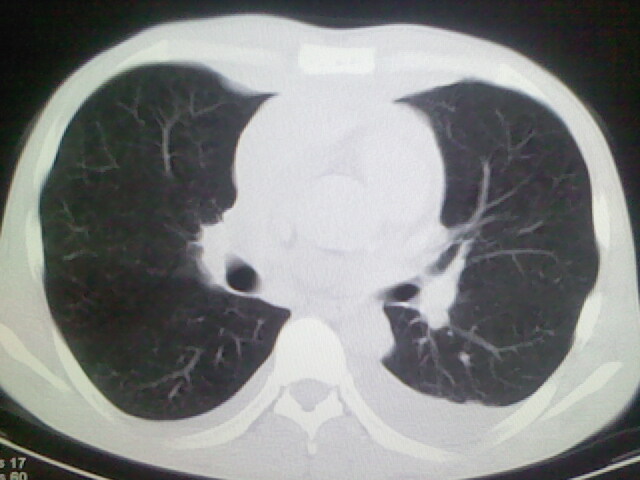

以下是引用杀毒软件在2008-9-3 6:11:00的发言:[br]侵袭性胸腺瘤------一般不侵到气管旁[br][br]考虑----纵隔淋巴瘤,心包及胸膜受累

以下是引用随光逐影在2008-9-3 7:07:00的发言:[br]1)考虑淋巴瘤可能。2)双侧胸腔积液(以左侧为甚)。3)心包积液。